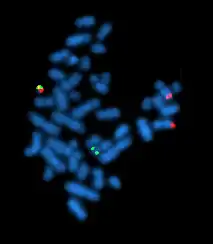

Cytogenetics is essentially a branch of genetics, but is also a part of cell biology/cytology (a subdivision of human anatomy), that is concerned with how the chromosomes relate to cell behaviour, particularly to their behaviour during mitosis and meiosis.[1] Techniques used include karyotyping, analysis of G-banded chromosomes, other cytogenetic banding techniques, as well as molecular cytogenetics such as fluorescent in situ hybridization (FISH) and comparative genomic hybridization (CGH).

In the 1980s, advances were made in molecular cytogenetics. While radioisotope-labeled probes had been hybridized with DNA since 1969, movement was now made in using fluorescent-labeled probes. Hybridizing them to chromosomal preparations using existing techniques came to be known as fluorescence in situ hybridization (FISH).[22] This change significantly increased the usage of probing techniques as fluorescent-labeled probes are safer. Further advances in micromanipulation and examination of chromosomes led to the technique of chromosome microdissection whereby aberrations in chromosomal structure could be isolated, cloned, and studied in ever greater detail.

Fluorescent in situ hybridization

Fluorescent in situ hybridization (FISH) refers to using fluorescently labeled probe to hybridize to cytogenetic cell preparations.

Analysis of FISH specimens is done by fluorescence microscopy by a clinical laboratory specialist in cytogenetics. For oncology, generally, a large number of interphase cells are scored in order to rule out low-level residual disease, generally between 200 and 1,000 cells are counted and scored. For congenital problems usually 20 metaphase cells are scored.